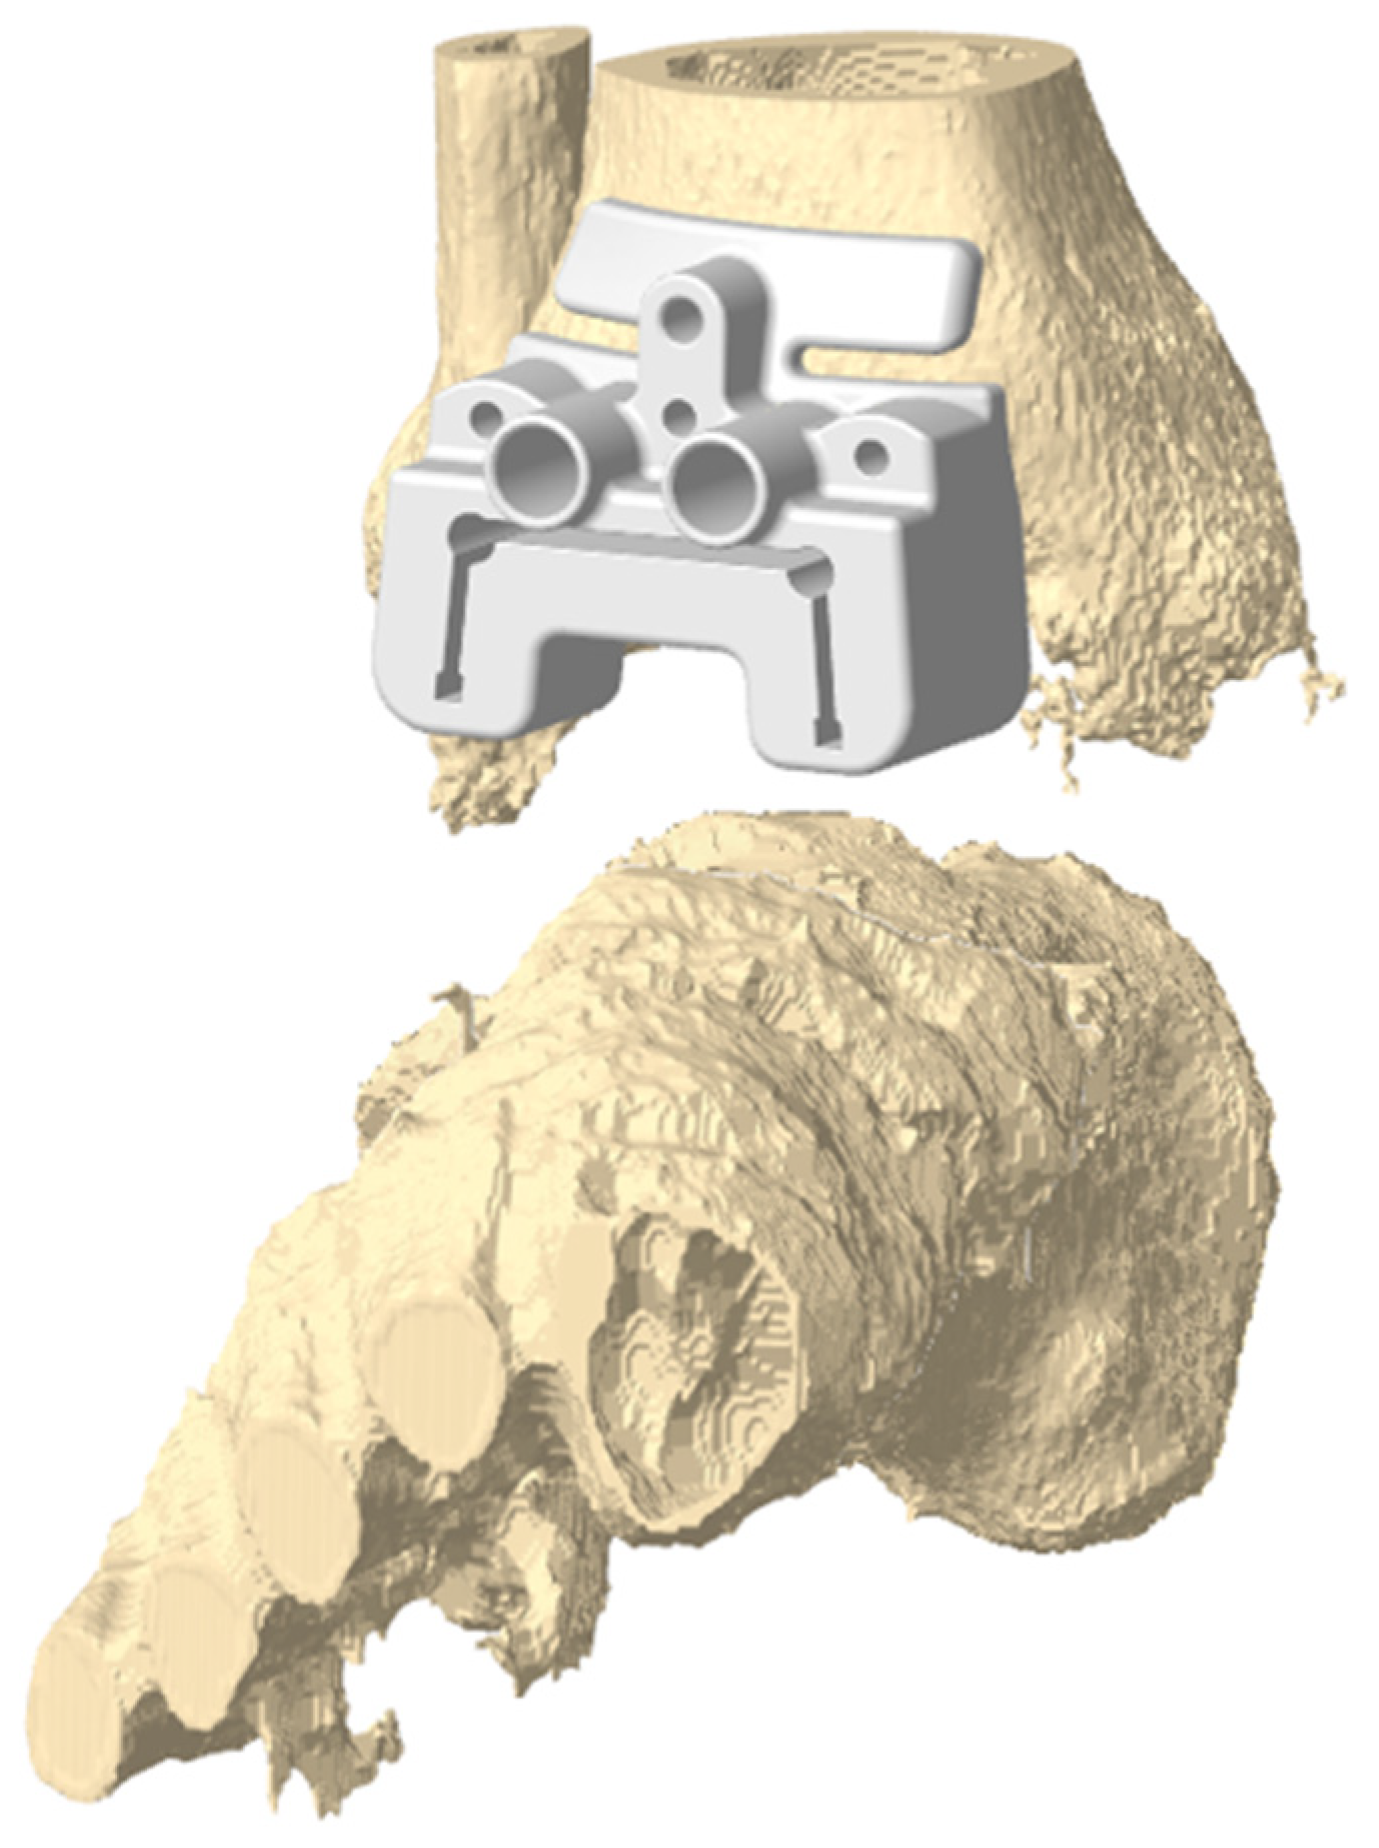

- Faldini, C.; Mazzotti, A.; Langone, L.; Arceri, A.; Bonelli, S.; Zielli, S.O.; Artioli, E. Custom-made total ankle arthroplasty with patient-specific instrumentation for severe bone loss conditions: A case series. Eur. J. Orthop. Surg. Traumatol. 2023, 34, 379–387. [Google Scholar] [CrossRef] [PubMed]

- Mazzotti, A.; Arceri, A.; Zielli, S.; Bonelli, S.; Viglione, V.; Faldini, C. Patient-specific instrumentation in total ankle arthroplasty. WJO 2022, 13, 230–237. [Google Scholar] [CrossRef]